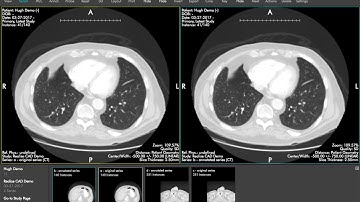

Real time Lung Nodule detection using chest CT slices with AI